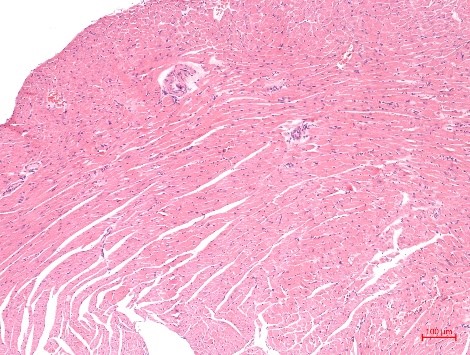

1、HE染色实验结果(小鼠肝脏-肺脏-心肌举例)

HE实验结果解读:细胞核呈现蓝色或者紫蓝色,细胞质和细胞外基质中的成分着红色。